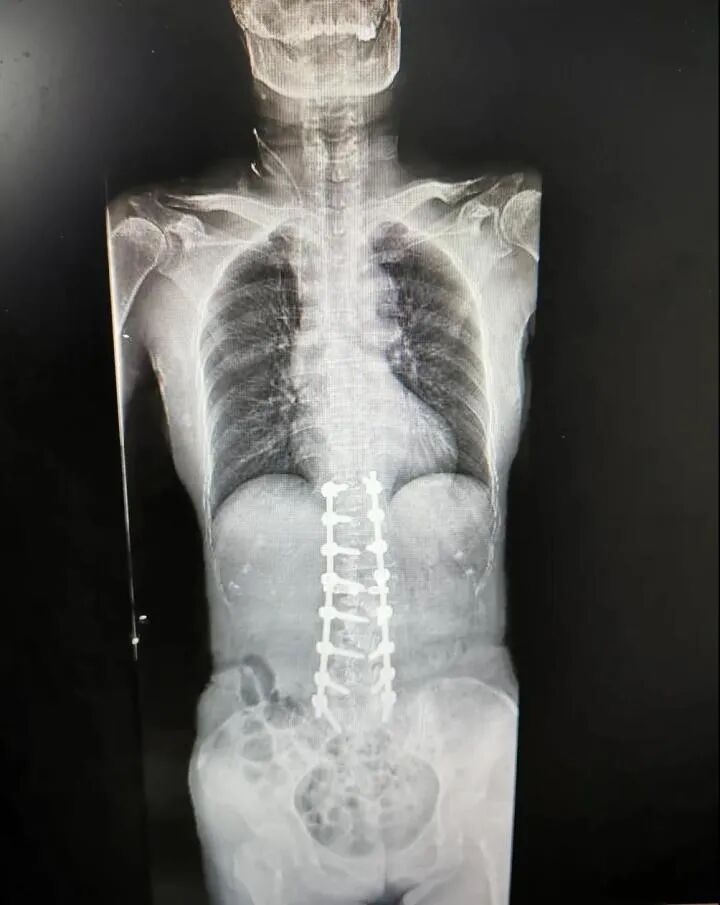

整个人驼得像虾一样

五脏六腑倒向一边

身体里植入十几颗钢钉后

身高“猛长”5厘米